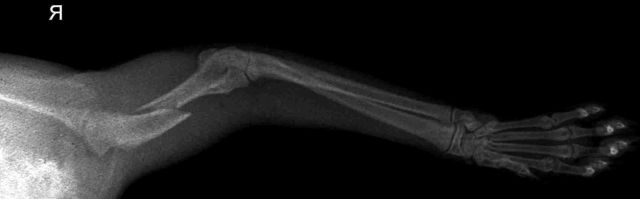

Пальпация пораженной области позволяет установить точное расположение повреждения. Важным этапом диагностики является рентгенография. При подозрении на осложненную травму, например, после ДТП, ветеринар может рекомендовать магнитно-резонансную томографию.

Диагностика в ветклинике

К методам диагностики относятся общий и биохимический анализы крови, рентген в двух проекциях и ЭХО сердца. В некоторых случаях может потребоваться УЗИ брюшной полости.